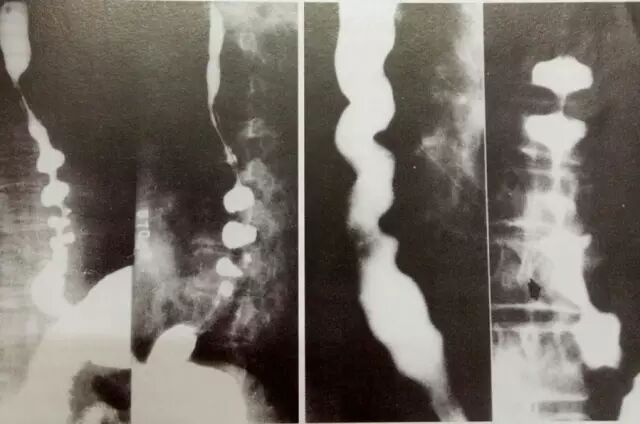

↑图:弥漫性食管痉挛